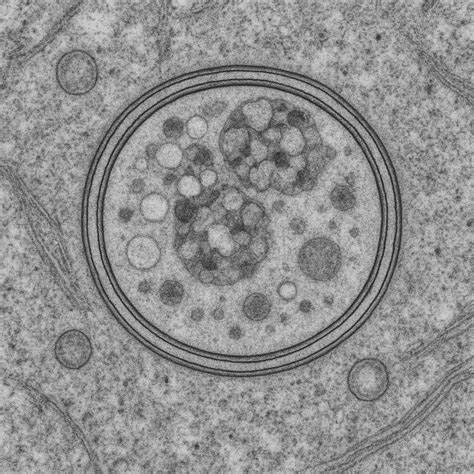

Problém etanolu spočíva v tom, ako pôsobí. Na rozdiel od iných drog, ktoré napodobňujú prirodzené látky v mozgu alebo pôsobia na špecifické receptory, presný mechanizmus účinku etanolu nie je úplne jasný. Keďže ide o malú molekulu, dostáva sa do celého tela difúziou. Kedysi panoval názor, že jeho účinok na centrálny nervový systém (CNS) je nešpecifický, no dnes je známych viac ako 20 potenciálnych miest účinku v mozgu. Viac ako 90 % konzumovaného etanolu sa metabolizuje v pečeni, zvyšok sa vylučuje močom, potom a dychom.

Po konzumácii sa etanol dostáva z tráviaceho traktu do krvi, ktorou je vedený do pečene. Už jeden drink dokáže zaťažiť pečeň a jej schopnosť metabolizovať etanol. V pečeni je etanol metabolizovaný alkoholdehydrogenázou na acetaldehyd, ktorý je toxický a karcinogénny. Následne je rýchlo premieňaný acetaldehyddehydrogenázou na acetát, ktorý je len mierne toxický a môže byť využitý ako alternatívny zdroj energie. Efekt alkoholu na dopamínový systém je zodpovedný za jeho vysokú návykovosť a vznik závislosti.

Alkohol sa do mozgu dostáva krvou, pretože ho nie je potrebné tráviť. Je to malá molekula, ktorá preniká do celého tela difúziou. Okrem iných mechanizmov pôsobí aj na GABAA receptory, podobne ako anestetiká.